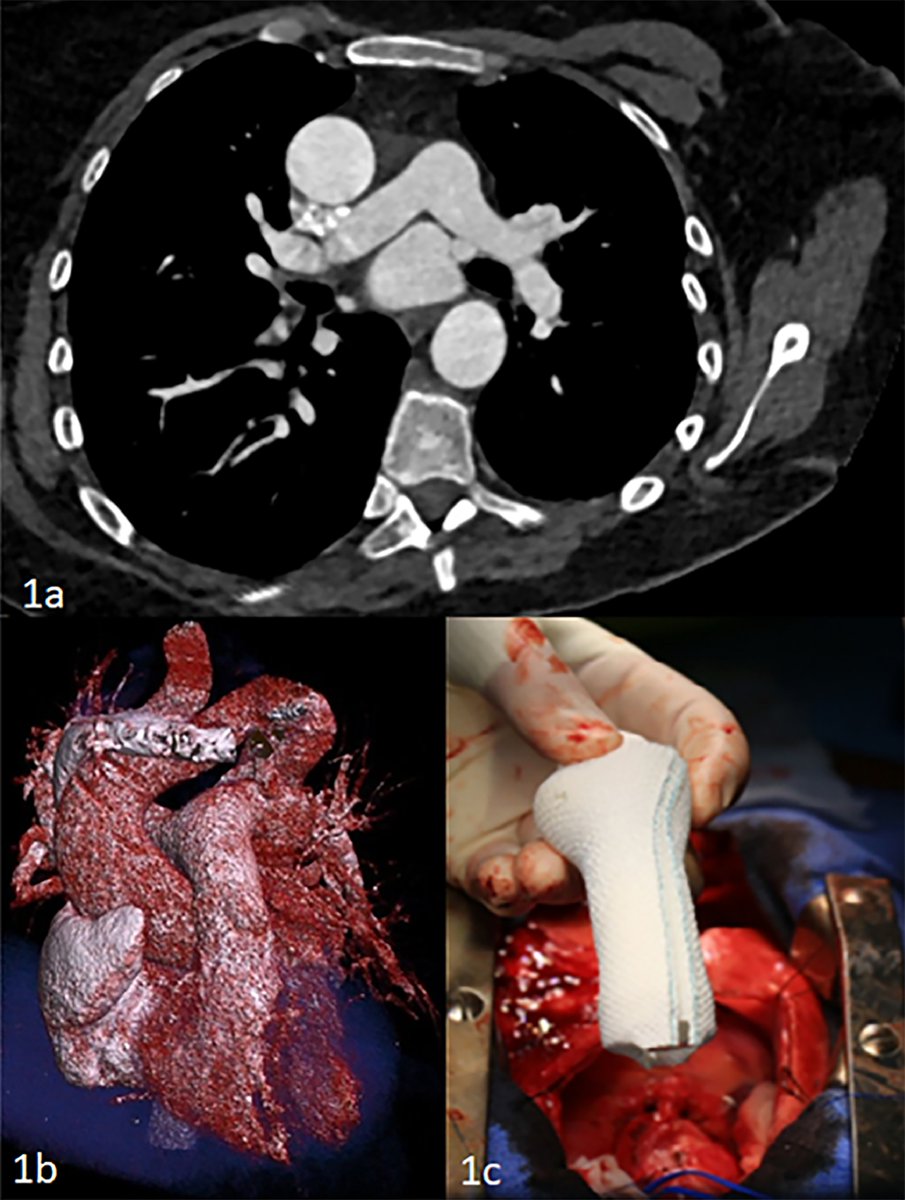

A recent multicenter analysis of aortic root replacement found that non-native chest increases the risk of postoperative mortality. However, surgeons found that prior root and true re-do root replacement do not add additional risk. Read more in #JTCVS: https://t.co/HeJYyD6pa8